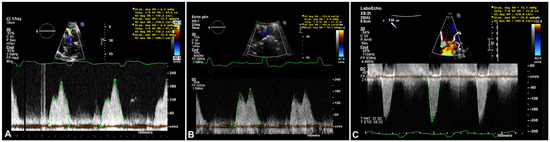

Myocardial infarction with nonobstructive coronary arteries (MINOCA): Myocardial infarction (MI) with non-obstructive coronary arteries (MINOCA) is defined as MI according to the fourth universal definition of MI [1] without coronary stenosis ≥50% on...